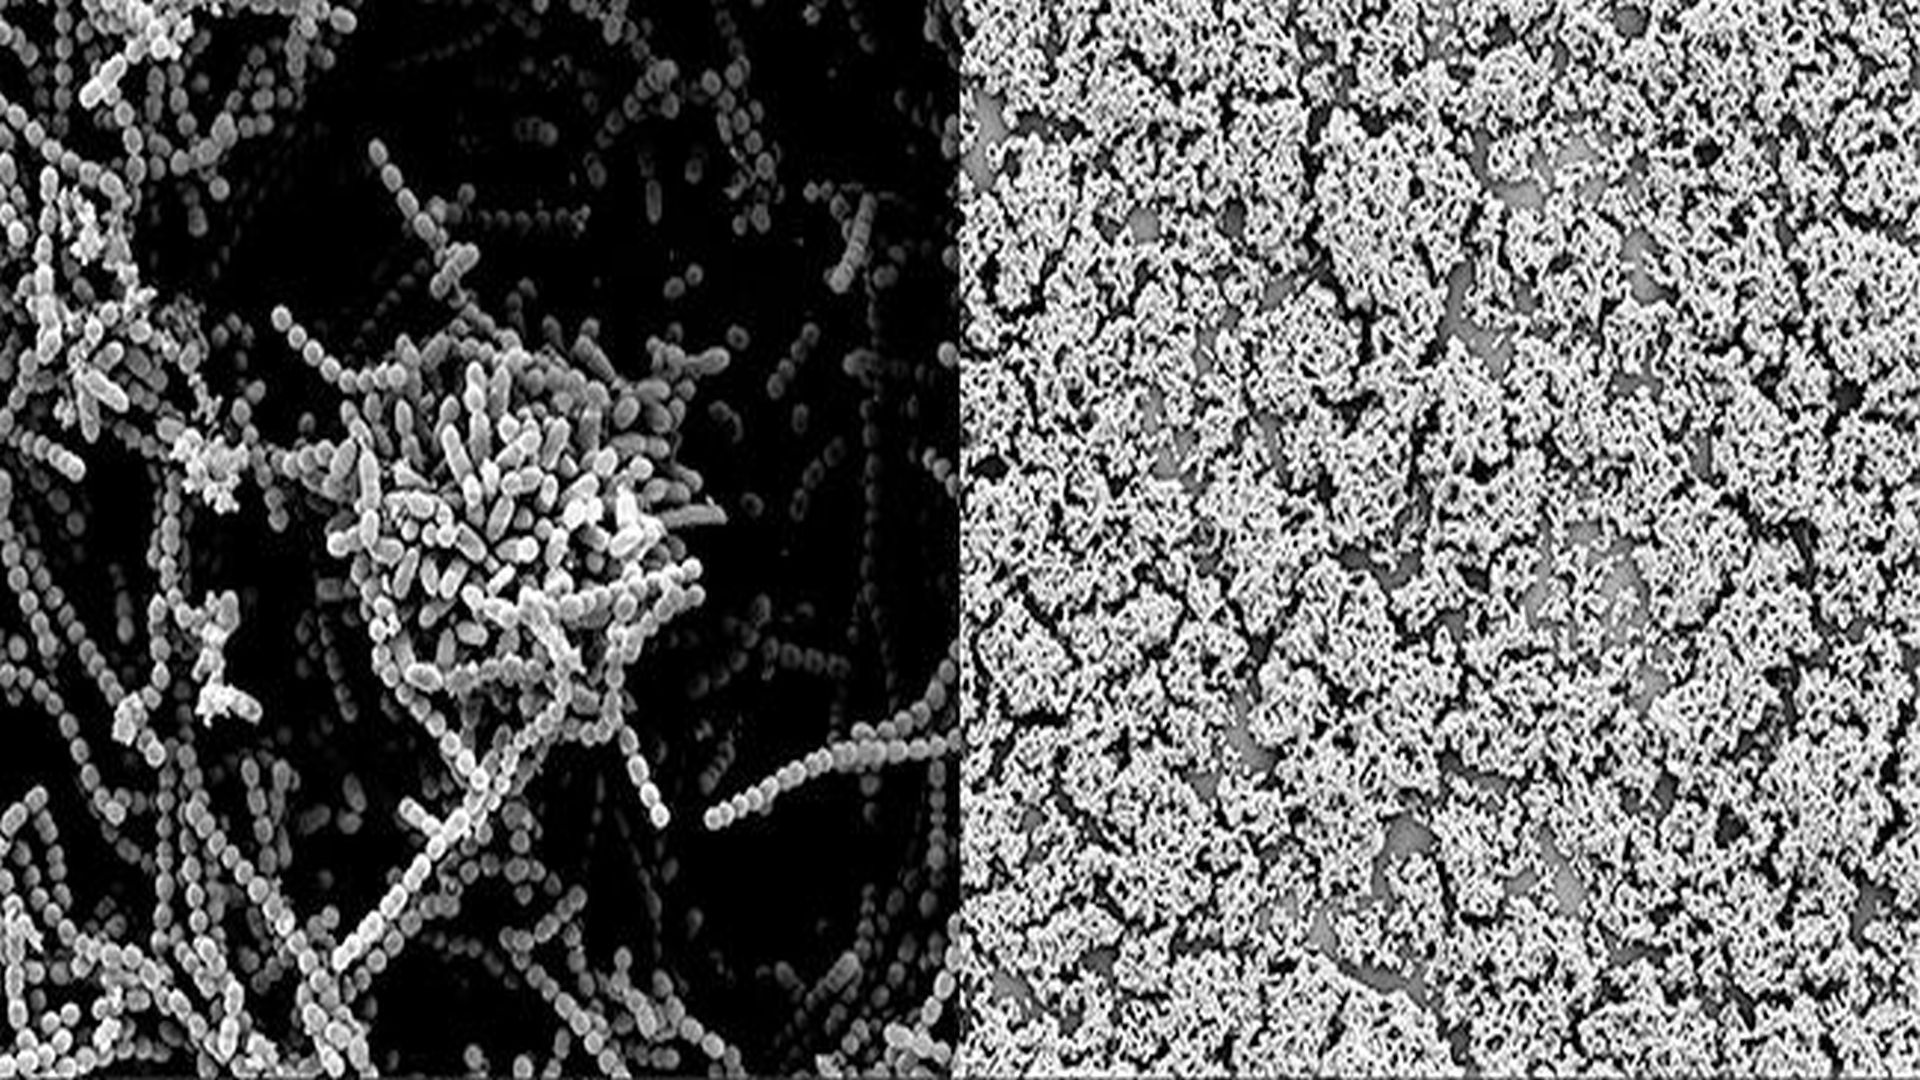

The close-up image on the left illustrates how Strep bacteria normally clump together to form a protective biofilm. The image of the right shows that the biofilm breaks down when a Strep culture is dosed with human milk sugars, exposing more of the bacteria to attack by antibacterial agents. Courtesy of Steven Townsend, Vanderbilt University

To do so, the researchers collected human milk carbohydrates, also called oligosaccharides, from a number of different donor samples and profiled them with a mass spectrometry technique that can identify thousands of large biomolecules simultaneously. Then they added the compounds to strep cultures and observed the result under the microscope. This showed that not only do some of these oligosaccharides kill the bacteria directly but some also physically break down the biofilms that the bacteria form to protect themselves.

In a pilot study, Townsend's lab collected five samples. They found that the sugars from one sample nearly killed an entire strep colony. In another sample, the sugars were moderately effective while the remaining three samples exhibited a lower level of activity. In a follow-up study, they are testing more than two dozen additional samples. So far, two broke down the bacterial biofilms and killed the bacteria, four broke down the biofilms but did not kill the bacteria and two killed the bacteria without breaking down the biofilms.

"Our results show that these sugars have a one-two punch," said Townsend. "First, they sensitize the target bacteria and then they kill them. Biologist sometimes call this 'synthetic lethality' and there is a major push to develop new antimicrobial drugs with this capability."

By dosing strep cultures with a mixture of milk sugars and antimicrobial peptides from human saliva, the researchers also showed that the sugars' ability to break down biofilms can also enhance the effectiveness of the other antimicrobial agents that breast milk contains.